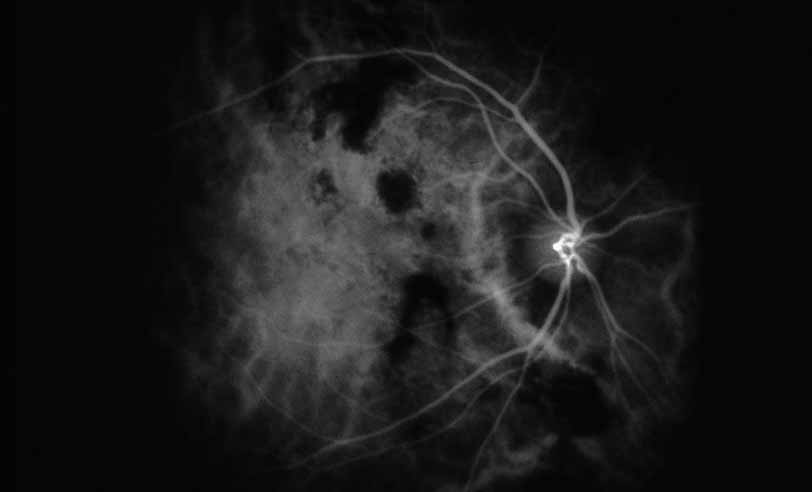

Fig. 1 Serpiginous choroiditis. Early frame of the fluorescein angiogram shows hypofluorescent and hyperflourescent patches extending outward from the optic nerve in a serpiginous pattern (Courtesy of Joseph Michaelson).

Fig. 2 Serpiginous choroiditis. Late frame of the fluorescein angiogram shows extensive staining of previously hypofluorescent zones, with continued hypofluorescence, characteristic of the acute phases of serpiginous choroiditis (Courtesy of Joseph Michaelson).